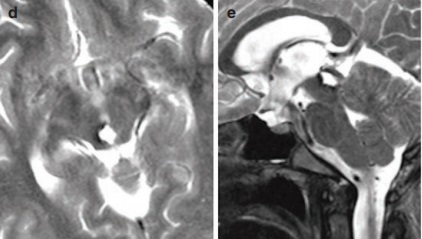

术中情况:在术中照片(g)上可以看到手术区域。通过幕下小脑上入路暴露病变。尽管小脑下降,但桥接小脑蚓部的静脉在硬膜内阶段结束前保持完整。在切除腔内没有可见海绵状血管瘤的残留部分(箭头)。

手术切除率:轴向(e)和矢状T2wMRI(f)记录了海绵状血管瘤的完全切除。